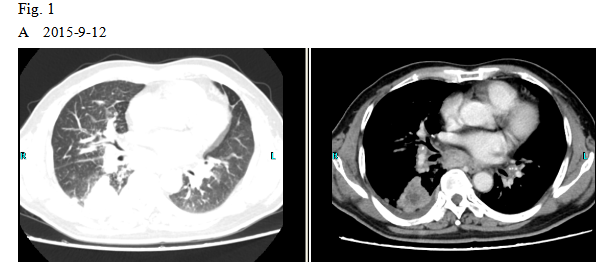

A 66-year old male patient with a smoking history was received by the Outpatient Department on September 14, 2015 due to “coughing for more than one month”. Main symptoms included a dry cough, a small amount of white phlegm, but freedom from fever, chest pains, bloody sputum, and any other discomfort. Stage IV-lung cancer is associated with anorexia and a loss of nearly 10 pounds. The patient had a poor constitution in the past, with a history of “acute hepatitis”, “type-2 diabetes” and “obsolete pulmonary tuberculosis”. The patient was accepted in the Department of Respiratory Medicine on September 15. The results of a lung CT scan indicated a “space occupied for posterior basal segment of right inferior lung and enlarged for mediastinal lymph nodes”. The patient was approved for a CT- guided transthoracic needle biopsy, immunohistochemistry, EGFR gene mutation detection, and systemic metastases assessment. He was diagnosed as “primary lung cancer, right lung adenocarcinoma, T4N3M1B (lung, pleura and brain), and stage-IV EGFR Exon 19 deletion mutation (Fig. 1A and Fig. 2A)”.

The patient checked for further treatment on November 23, 2015. A pre-chemotherapy assessment was made and the results showed multiple bone metastases and multiple enlarged lymph nodes in the left shoulder blade, the fourth lumbar, the right iliac bone and other locations. Performance status (PS) was only one point. Pemetrexed Disodium (500 mg/m2 d1) + Carboplatin (AUC 5 d1) + Bevacizumab (7.5 mg/Kg d1) was administered beginning November 26, 2015 for the chemotherapy treatment and supportive therapy was provided, such as, dehydration, reduction of intracranial pressure, promotion of bone repair, pain relief, and waist protection. After discharge, the coughing basically disappeared and the dizziness, backaches, and hemiparesthesia of the left side were significantly improved. Patient emotional state and sleep quality was significantly improved. It was basically normal after a routine blood examination. A second chemotherapy treatment was successfully completed on December 18 (the program is idem). The patient returned to the hospital on January 6, 2016 and was proposed for a third chemotherapy. The pre-chemotherapy assessment showed that the measurable, targeted right lung lesion had decreased (3.2 mm, with a rate of decrease 44.8 %) (Fig. 1D). Lymphangitis carcinomatosa was significantly decreased and right frontal nodulus lesions were reduced significantly (Fig. 2C). No new lesions were found. Efficacy was assessed as partial relief (PR). A third and fourth chemotherapies were completed on January 9 and January 30, 2016. Efficacy was re-assessed as PR (Fig. 1E) with lung CT review as an outpatient on February 11. Since then, the patient had been subjected to a combined administration program of pemetrexed disodium (500 mg/m2 d1) + bevacizumab (7.5 mg/Kg d1) for continued chemotherapy. A lung CT and a cranial MRI were peformed on April 16. The results showed that the control of lung lesions and intracranial lesions were basically the same as before (Fig.1F and Fig. 2D). The patient had no cough, backaches, or hemiparesthesia and the quality life significantly improved. PS was decreased to zero.